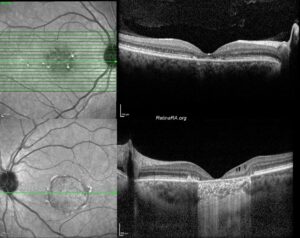

Pigmented Paravenous Retinochoroidal Atrophy

This case was a 33-year-old male patient whose best corrected visual acuities were 20/25 for [...]